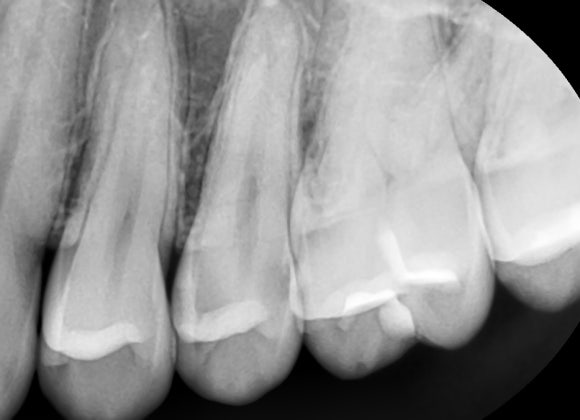

증상과 상태에 따라 큐레이, 치근단 X-ray, CT 등을 적절히 활용하여 문제의 원인을 다양한 방법으로 확인하는걸 원칙으로 있습니다.

치근단 x-ray 촬영 사진